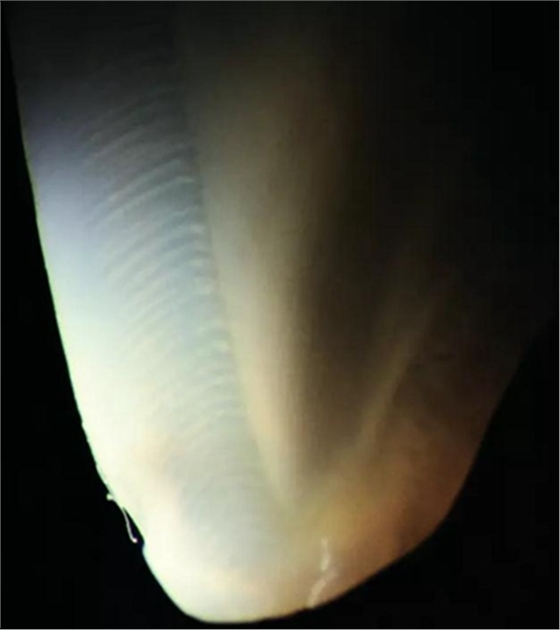

圖2.40顯微鏡下查看天然牙齒切片透照:

白色的(釉柱間質)和天藍色的(釉柱)薄層非常明顯。